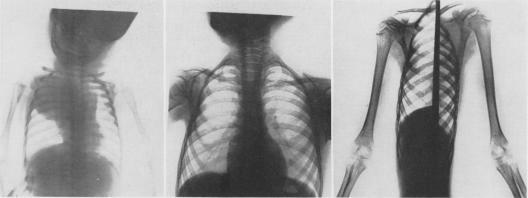

Intrathoracic neurogenic tumors in infants and children; a study of forty cases.

Ann Surg. 1959 Jul;150(1):29-41. doi: 10.1097/00000658-195907000-00003.